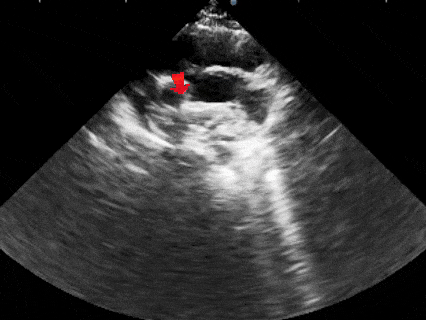

左盘展开

DSA下前推钢缆,后撤鞘管,使左盘面3个Mark点及腰部Mark点推送至鞘管外

牵拉成型线使左盘面成型,并后撤钢缆和鞘管使左盘面贴靠在房间隔